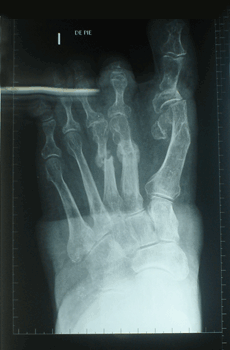

RESULTADOS

Caso 1: Hallux Valgus del Adulto